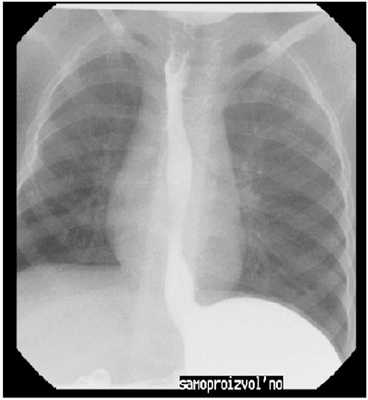

Пальпация области шеи, рентгенография пищевода простая и контрастная. Контрастные инородные тела видны при обзорной рентгеноскопии и рентгенографии грудной клетки. При подозрении на заглатывание неконтрастного инородного тела проводят исследование с контрастным веществом (больному дают одну чайную или десертную ложку густой бариевой взвеси, затем он делает 2-3 глотка воды, в норме вода смывает барий, но при наличии инородного тела часть контрастного вещества задерживается на нем - способ СВ. Ивановой-Подобед). При локализации инородного тела в шейном отделе пищевода выполняют боковую рентгенографию гортаноглотки в проекции Г.М. Земцова, позволяющую также диагностировать сопутствующие воспалительные изменения околопищеводной области. При локализации неконтрастных инородных тел в грудном и диафрагмальном отделах пищевода определяют "симптом слепка" - маятникообразные движения контрастной взвеси - движение вверх при глотании фиксированного на инородном теле контраста.

С точки зрения врача рентгенолога обычного рентгеновского кабинета, оборудованного первым рабочим местом (скопией) ожидаемая скеалогическая картина, которая может иметь место, это перераспределение введенного рентген-контрастного вещества из желудка в пищевод, как самопроизвольное, так и спровоцированное в отсутствии позывов на рвоту. В данном случае можно говорить лишь о забросе содержимого желудка в пищевод [6]: гастроэзофагальный рефлюкс (ГЭР).

Применяемая методика рентгеновского выявления ГЭР проводится в соответствии с методическими рекомендациями Министерства здравоохранения СССР 1981 год [1].

При отрицательных результатах пациент осматривается в положении Тренделенбурга (головной конец стола опускается вниз на 10-110, входит в «стандарт» диагностики в 1969 г., О.С. Радбиль).

Данный приём позволяет, увеличить процент выявляемости ГЭР и, особенно грыжи пищеводного отверстия диафрагмы [9], в частности, скользящую.